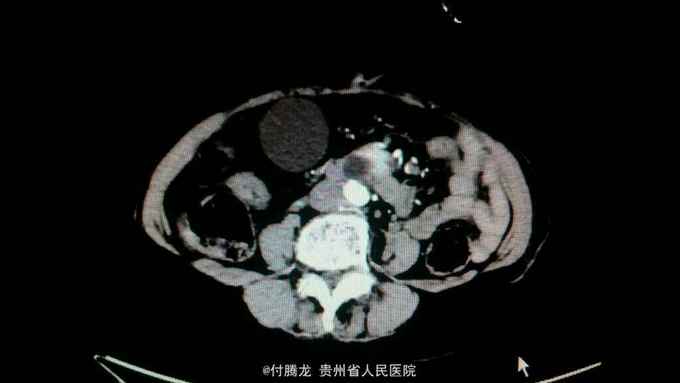

全身黄染伴乏力2月 病史:患者2月前无明显诱因下出现乏力,无恶心呕吐,畏寒发热等,后逐渐发现全身皮肤黄染。遂至当地医院检查。腹部ct提示胆总管下段狭窄,不排除炎性狭窄。胆红素200+。为进一步治疗来我院。

查体:全身皮肤及巩膜重度黄染,上腹轻压痛。 辅助检查:胆红素234,直接胆红素106,间接胆红素128。ALT60,AST88。肿瘤指标199及AFP正常。腹部ct提示胆总管肠内段高密度结节,不排除结石。超声內镜提示胆总管下段梗阻,考虑壶腹部肿瘤。MRCP提示十二指肠壁内段梗阻。